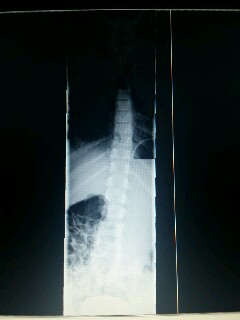

es geht um meine Tochter, sie wird im Februar 7 Jahre alt. Sie leidet seit sie 4 Jahre alt ist unter juveniler Arthritis ( Kinderrheuma) durch die Gelenkentzündungen im Knie hatte sie eine Beinlängendifferenz von fast 1cm. Dadurch stimmte die ganze Statik nicht mehr. Leider hat unser Physiotherapeut jetzt definitiv eine Skoliose festgestellt. Da wir in Gießen eine Wartefrist beim Orthopäden von fast 5 Monaten haben, kontaktierte ich die Praxis von Dr. Hoffmann in Leonberg wo wir am 29.2 hin können. Ich weiss dass ihr keine Fachärzte seid, möchte aber trotzdem wissen wie ihr die Skoliose einschätzt. Im Anhang ein paar Bilder.

PS: Die Röntgenbilder sind vom Sommer 2014 aufgrund der Beinlängendifferenz erstellt worden. Aktuelle haben wir noch nicht.

ich bin natürlich kein Arzt und hab auch mit Skoliose wenig Erfahrung, aber das, was man auf dem Röntgenbild sehen kann sieht meiner Meinung nach nicht nach einer starken Skoliose aus sondern eher nach einer skoliotischen Fehlhaltung, vielleicht verursacht durch die Arthritis.

Was ich aber sehe (auf dem zweiten Bild) scheint mir ein starkes Hohlkreuz zu sein. Wenn ich das richtig interpretiere.

wie auch Thomas sehe ich keine ausgeprägte Skoliose auf dem Röntgenbild. Mir sieht irgendwie die gesamte Wirbelsäule schräg aus (evl. Folge der Beinlängendifferenz), der obere Teil des Röntgenbildes ist schlecht zu sehen. Auf dem zweiten Bild sieht es mir auch nach einem starken Hohlkreuz aus.

auf den Rö-Bildern ist in der Tat "nur" eine skoliotische Fehlhaltung zu erkennen, jedoch eine idiopathische Skoliose. Auch wenn dies am Monitor nur schlecht zu beurteilen ist.

Und natürlich die sehr starke Lendenlordose ("Hohlkreuz").